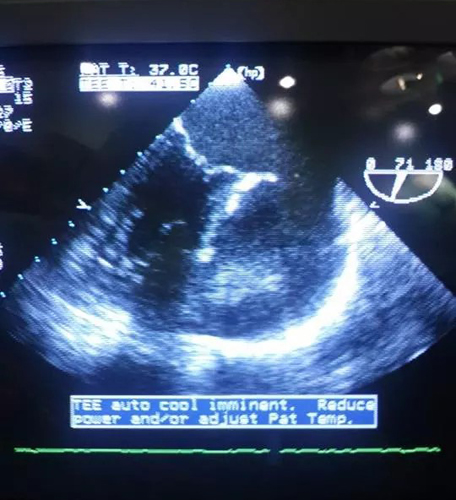

ЭхоКГ: Полостное образование размерами 7 x 8 см, сообщающееся с ушком левого предсердия и содержащее в своей полости округлое плотное образование размерами 5 x 6 см (тромб?). Образование сдавливает стенку левого предсердия и боковую стенку левого желудочка.

КТ: Полостное образование размерами 7 x 8 см, сообщающееся с ушком левого предсердия и содержащее в своей полости округлое плотное образование с ровными контурами и участком обызвествления внутри, размерами 5 x 6 см (тромб?). Образование сдавливает стенку левого предсердия и боковую стенку левого желудочка.

19.02.15г. под руководством зав. отделением кардио-хирургии В. Гаспаряном, при непосредственном участии ведущих врачей отделения (А. Айрапетяна, А. Севояна), а также профессора из Швейцарии П. Вогта была произведена операция, во время которой было обнаружено огромное полостное образование, исходящее из ушка левого предсердия, более всего напоминающее дивертикул. Произведено иссечение дивертикула с извлечением огромного овального образования из его полости, более всего похожего на белый тромб (5 x 6 см). Отмечается восстановление нормального синусового ритма сразу же после иссечения дивертикула на операционном столе.